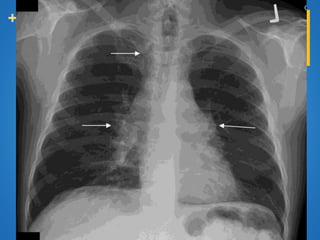

Paradoxical response

 One of the distinguishing features of sarcoidosis.

Nodal

enlargement Lung

disease